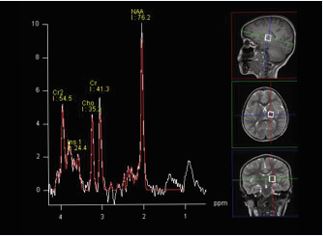

MRI technique: The protocol consisted of axial T1, axial FLAIR, axial DWI, axial SWI, coronal T2, and sagittal T1 sequences. Proton MR spectroscopy was performed in all patients by using a single voxel point-resolved spectroscopy (PRESS) sequence with a repetition time (TR) of 1500 ms and two echo times (TE) of 144 milliseconds (ms) and 35 ms, voxel size of 15 mm were used. As illustrated in Figure A and B, two locations were assessed with both the long and short TE MRS. One in the frontoparietal deep white matter and the other in the basal ganglia. The metabolites assessed include NAA, choline, creatine, myo-inositol, and lipids/lactate. All MRI examinations were reviewed by an experienced pediatric neuroradiologist.Data were coded and recorded in an Excel spreadsheet program. Statistical Package for the Social Sciences (SPSS) software, Version 27.0.0.0 (IBM Corp., Armonk, NY) was used for data analysis. A descriptive analysis of the experience of the participating groups was provided.

Figure B: Single-voxel PRESS acquisition in the basal ganglia.